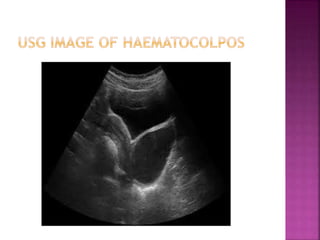

 Amenorrhea

 Periodic pain in the lower abdomen

 Abdominal lump

 Retention of urine